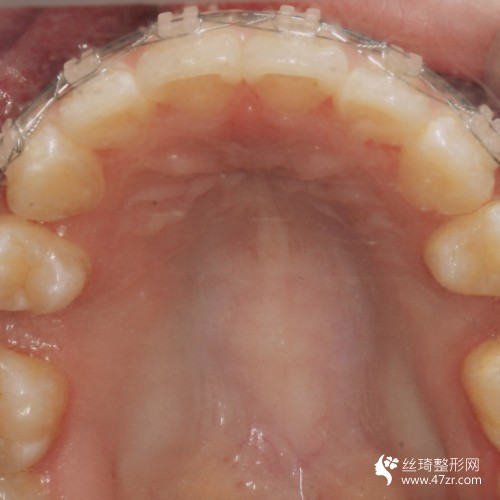

3.手術(shù)案例介紹

術(shù)前:因為我的牙齒很不好看,所以這種情況給我的外在形象帶來了很大的影響,為了改變我決定到醫(yī)院去做手術(shù),醫(yī)師根據(jù)我的情況給我做了牙齒矯正手術(shù)的方案,看到手術(shù)方案之后,我就決定在昆明美奧口腔醫(yī)院做手術(shù),因為這所醫(yī)院很正規(guī),而且醫(yī)生也是很專業(yè)的,所以我覺得完成手術(shù)之后的果會很不錯。

術(shù)中:在進行手術(shù)過程中是比較沒問題沒多少痛感的,因為醫(yī)生的手法很輕柔,所以我覺得手術(shù)過程還是比較理想的,醫(yī)生說手術(shù)恢復(fù)起來會比較慢,讓我聽他的話好好的進行護理。

術(shù)后7天:這幾天一直在聽醫(yī)生的話進行很好的護理,沒有吃堅硬的東西,也沒有吃一些太油膩的食物,所以手術(shù)的恢復(fù)還算不錯吧,但是這才是剛開始醫(yī)生說要慢慢的去恢復(fù),不要心急,所以我也就只能慢慢的等待了。

術(shù)后90天:很多朋友都說我現(xiàn)在的恢復(fù)是比較不錯的,因為整體看上去更加好看了,我也覺得是這樣的,雖然手術(shù)還沒有得到完全的恢復(fù),但是可以看出來有了很好的改良。

術(shù)后160天:手術(shù)結(jié)束之后不但使我的牙齒得到了很好的矯正,而且我整個人的形象也變得更美觀了,所以我對手術(shù)是感到很滿意的,真的很感謝醫(yī)生,現(xiàn)在手術(shù)的恢復(fù)還沒有完全的恢復(fù)好,所以還是需要進行很好的護理。

術(shù)后365天:手術(shù)恢復(fù)的差不多了,今天到醫(yī)院去復(fù)診的時候,醫(yī)生說恢復(fù)的很好,在整個手術(shù)過程中都沒有出現(xiàn)任何不良的情況,真的是太滿意了,很感謝曾強醫(yī)生。